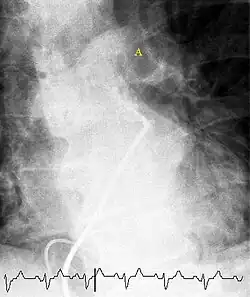

Fluoroscopic pulmonary angiography

Selective pulmonary angiogram revealing clot (labeled A) causing a central obstruction in the left main pulmonary artery. ECG tracing is shown at the bottom.

Historically, the gold standard for diagnosis was pulmonary angiography by fluoroscopy, but this has fallen into disuse with the increased availability of non-invasive techniques that offer similar diagnostic accuracy.[71]